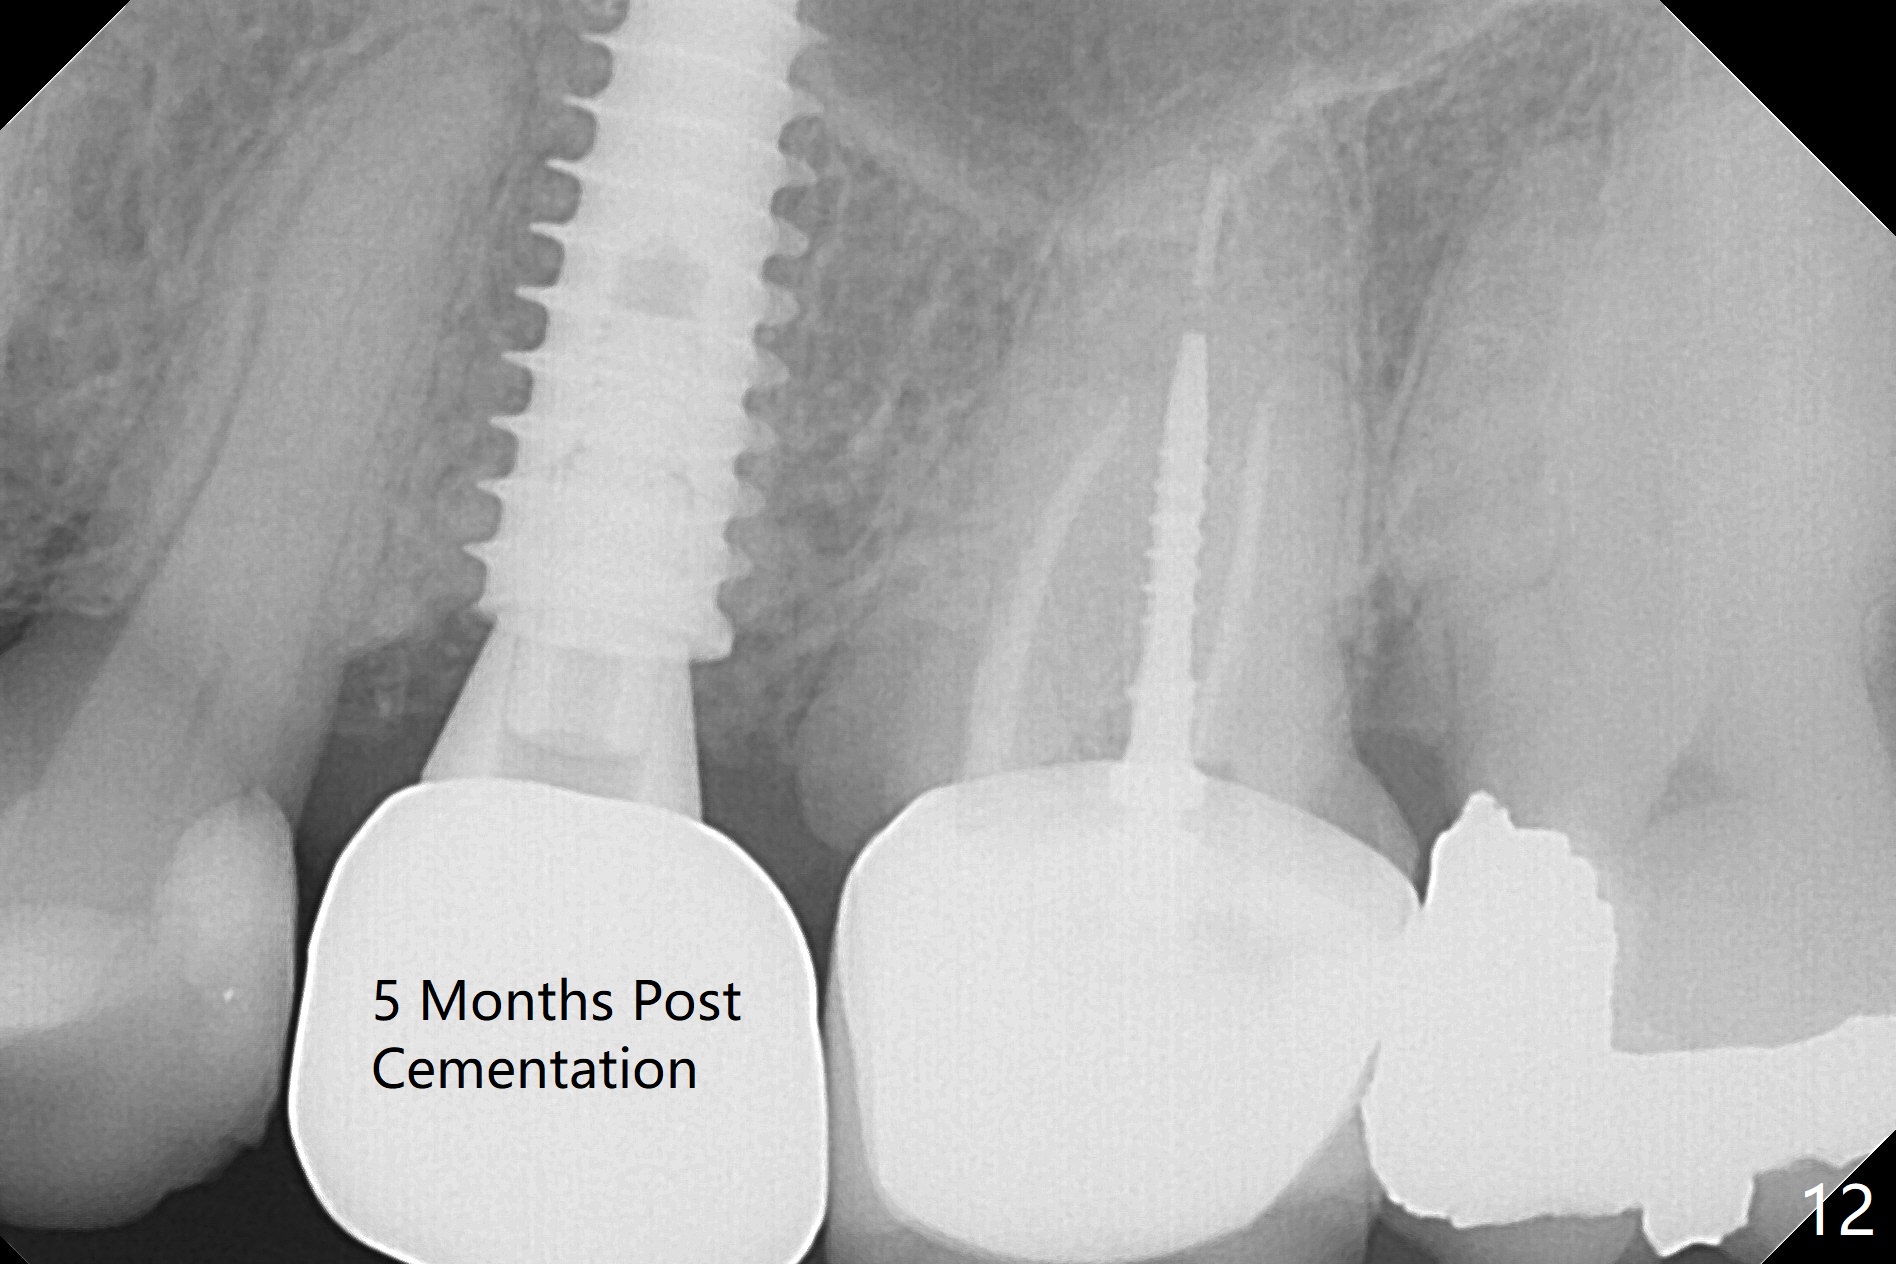

Since the apical native bone is limited at #13 after extraction, no PA is taken until a 4x11 mm dummy implant is placed after 1.6 mm and 3.3 mm drills for 13 mm (Fig.1). After using Lindamann bur to move the osteotomy distal and reusing 3.3 mm drill, the trajectory of a 4.5x11 mm IBS dummy implant improves (Fig.2,3 with low stability). When the implant is removed, the buccal portion of the socket is found to be perforated (Fig.4 P). Although the reason for the perforation is unknown, it is repaired by insertion of a piece of PRF plug, followed by allograft. #1 and 2 in Fig.4 represent the 1st and 2nd osteotomies, as shown in Fig.1 and 2, respectively. The trajectory of the final 5x13 mm implant is acceptable (Fig.5-7, different angulations), so is insertion torque (45 Ncm). After placing a 5.5x4(4) mm abutment, an immediate provisional is fabricated (Fig.8 P) with occlusal clearance (*). The interdental papillae remain in place 12 days postop (Fig.9 *). There is no sign of postop sinus infection. The provisional is loose 18 days postop; the abutment is changed to 5x4(3) mm (Fig.10). It is difficult to catch the mesial margin of the abutment for impression 4 months postop, due to poor oral hygiene and the short cuff (3 mm, Fig.11). The appointment for impression is rescheduled with emphasis on oral hygiene and no wearing the provisional for a few days prior to next appointment. Bone has grown into the space between the 1st and 2nd threads 5 months post cementation (Fig.12) and the bone is normal, solid and dense 2 years 11 months post cementation (Fig.13 >). There is mesial open margin of the tooth #14 (Fig.13,14 *).